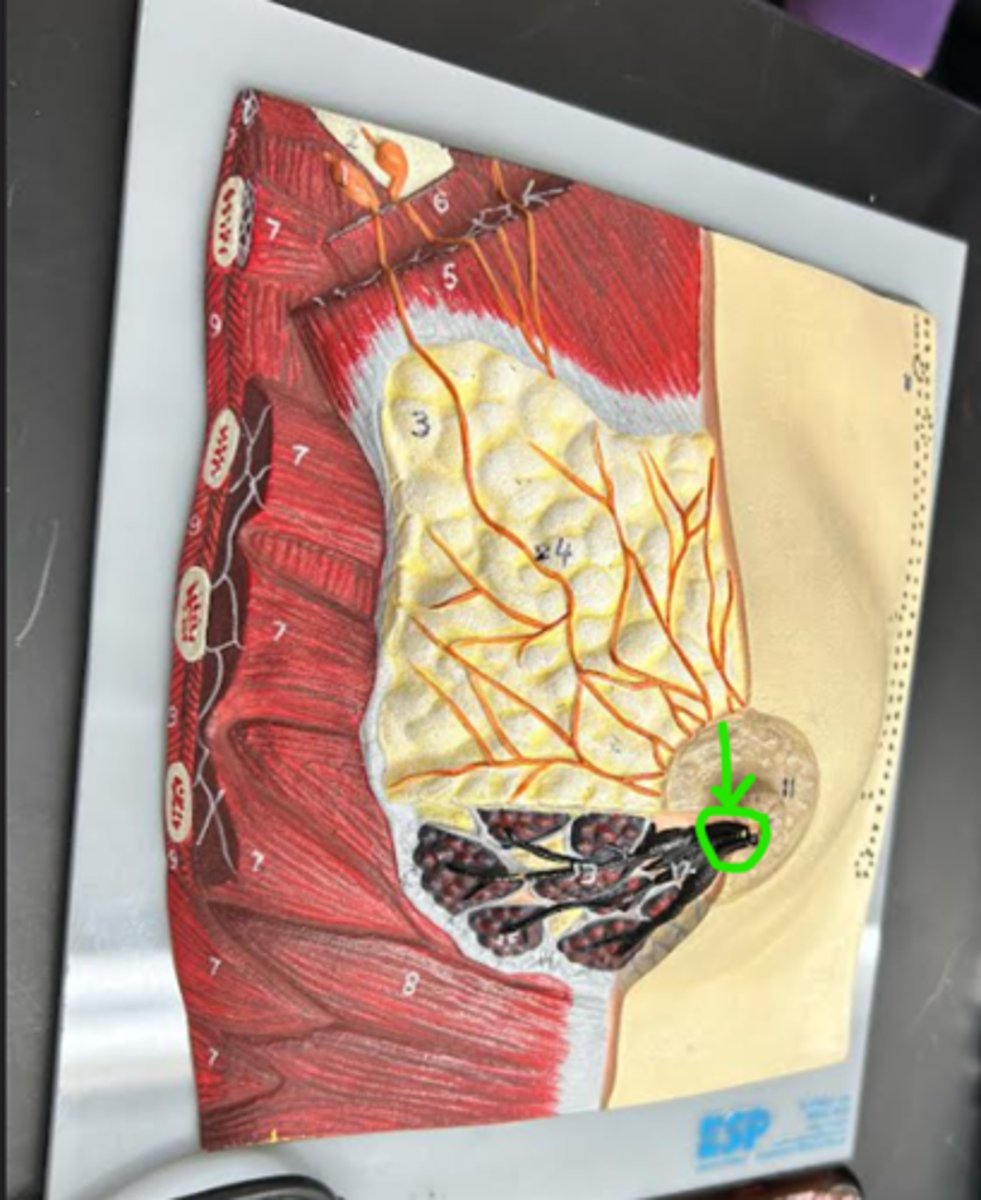

Breast

whole structure/ model

Areola

Nipple

Lactiferous sinus

Lactiferous duct

Mammary lobe

Mammary lobule